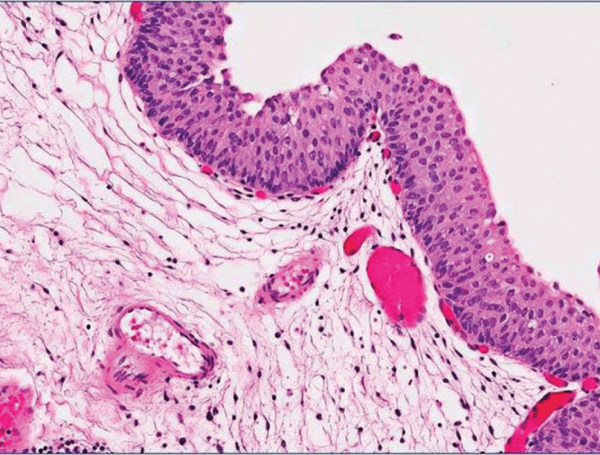

Mesane kazıma ameliyatı, TUR-M (TUR mesane) ameliyatı, kapalı mesane tümörü ameliyatı olarak da bilinir. TUR-M ameliyatı idrar kanalından kamera ile girilerek mesanedeki tümörlerin çıkarılması işlemidir. Üretra yani idrar kanalından girilerek